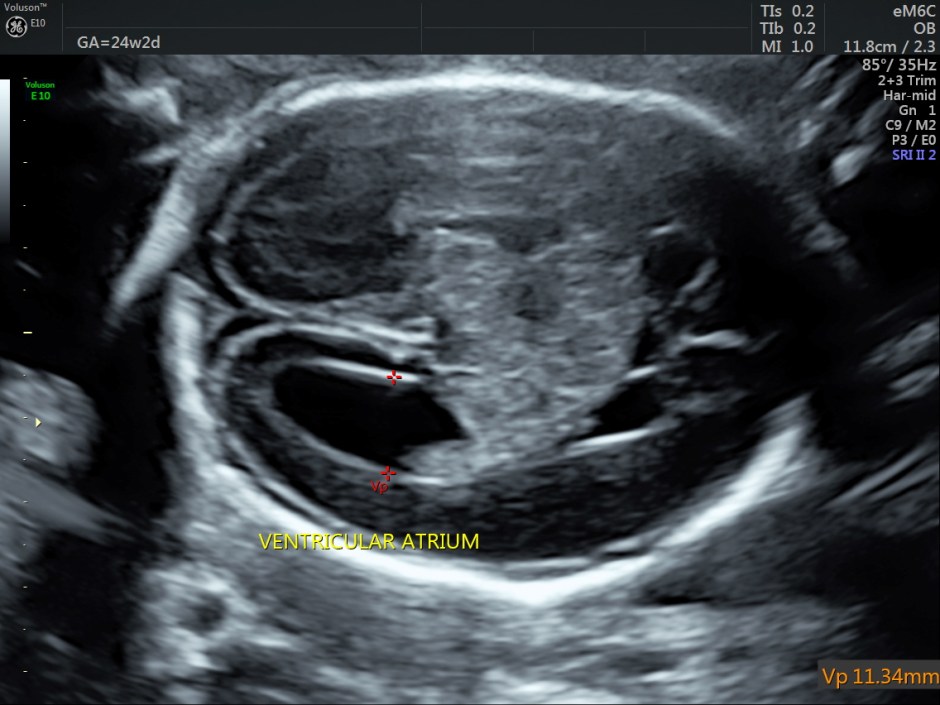

Her BPD ( 6.5 % tile) and HC ( 7 % tile) were less than 10 % tile. Mild ventriculomegaly was seen. ( 11.34 % tile).

A careful look at the 3rd ventricle shows a solid mass.

Choroid plexus papilloma (CPP) is a rare and benign tumor composed of epithelial cells that line the ventricular choroid plexus and correspond to 0.4%-0.6% of fetal intracranial tumors. CPP may develop in the lateral ventricle, third ventricle, and fourth ventricle. It is generally diagnosed during the third trimester and is always associated with unilateral or bilateral ventriculomegaly. CPP has slow growth and noninvasive behavior; however, because of its specific location, CPP can block the drainage of cerebrospinal fluid and cause hydrocephalus.

An echogenic mass involving the choroid plexus is visualized on US and MRI. Color Doppler imaging may be useful to show vascularization in the lesion.